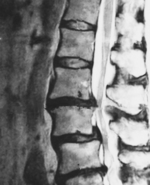

当院は腰痛や椎間板ヘルニア、脊柱管狭窄症、坐骨神経痛の痛みなどの症状でお悩みの方が多く来院しています。そのほか、肩こりや膝、股関節の痛みなども対応しております。

【ヘルニア・狭窄症】

早朝に出る、お尻〜もも裏の激しい痛みが改善!

【腰痛・狭窄症】

脊柱管狭窄症と診断され、長年続いた腰痛

今は痛くないです!